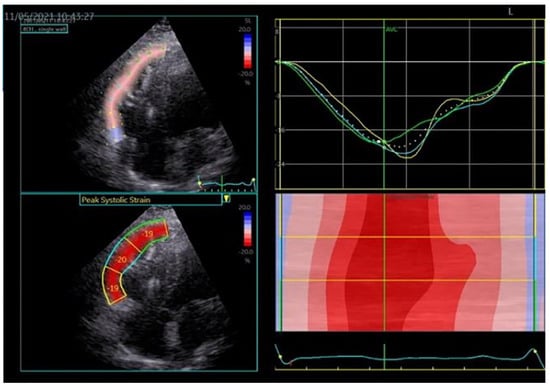

4. Hypertrophic Cardiomyopathy